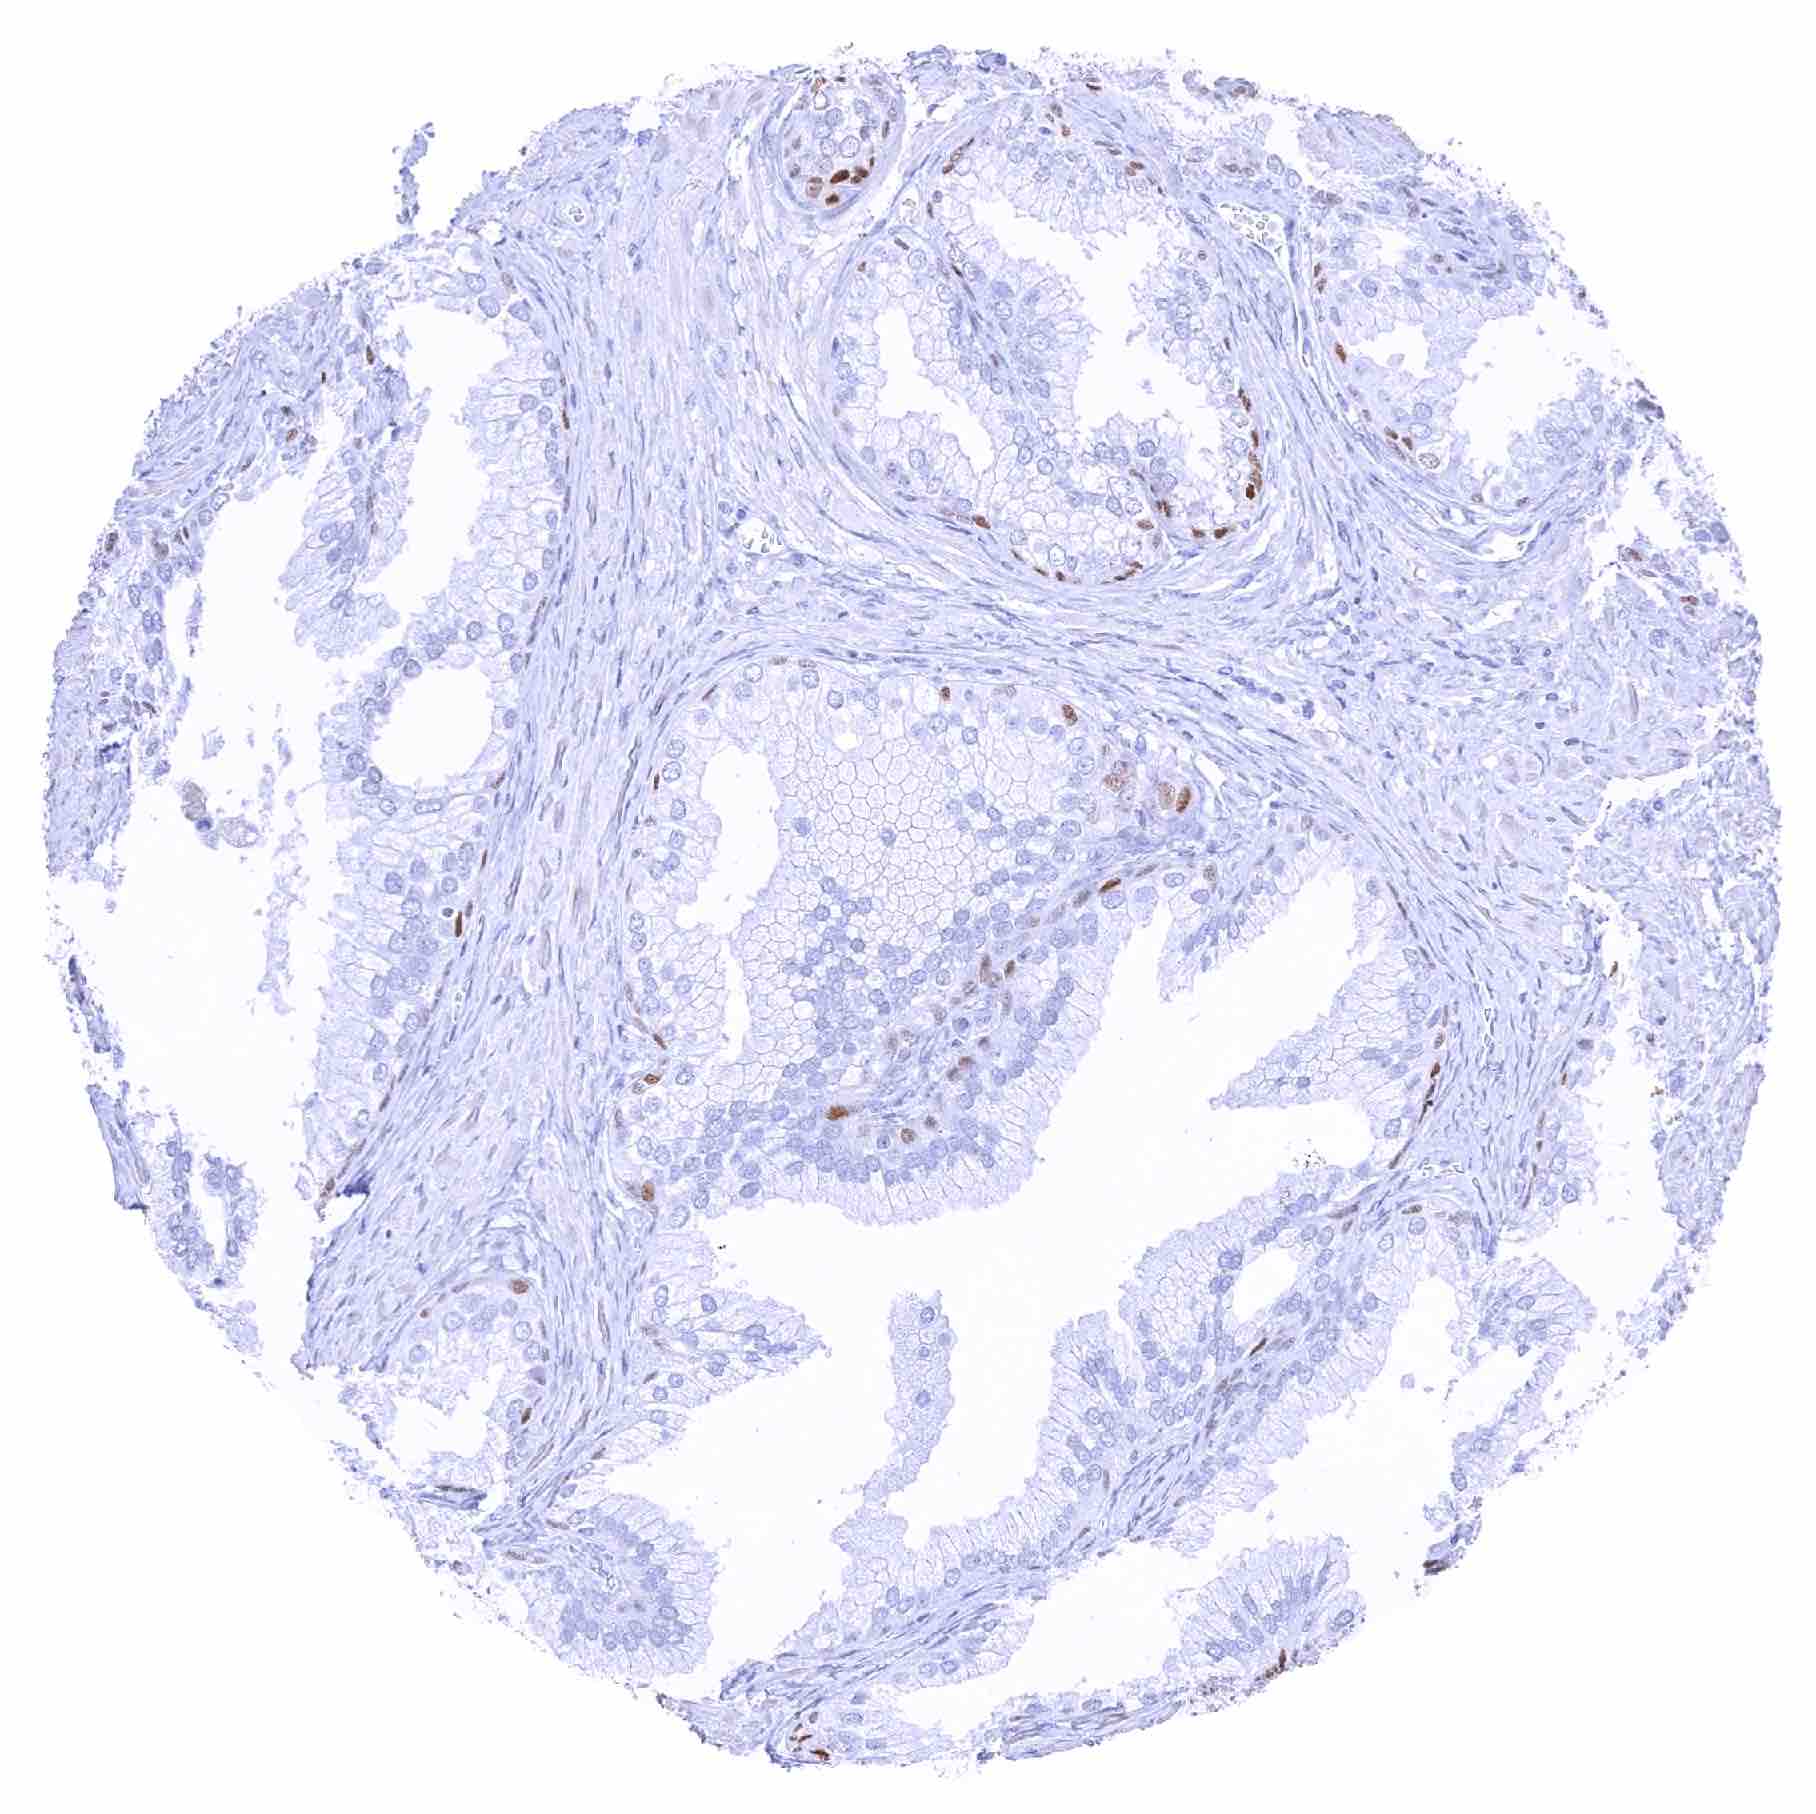

Prostate – Strong SOX2 positivity of a fraction of basal cells